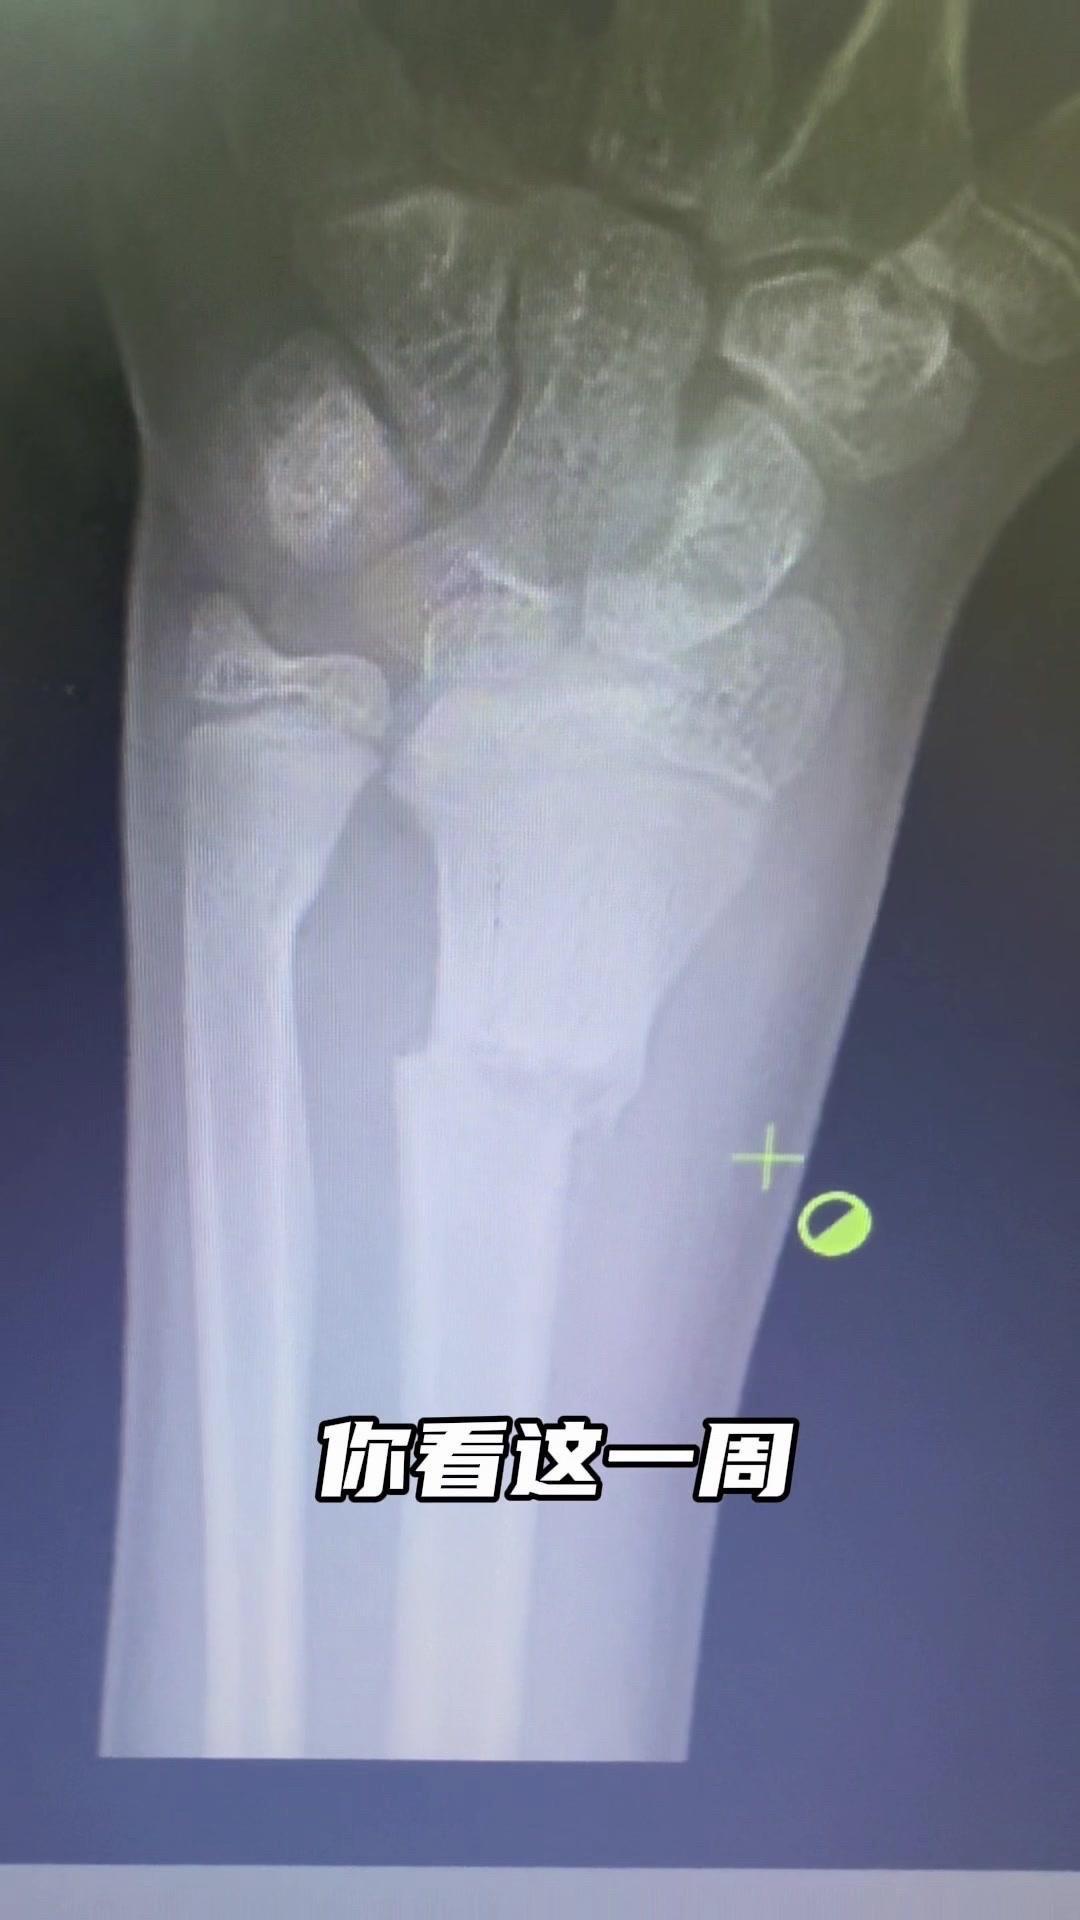

儿童骨折别拖延!💡上周接诊一个10岁女孩,摔了一跤后腕部疼痛还伴有畸形,家长觉得是小伤没在意,结果一周后孩子疼得更厉害,畸形也更明显了。来医院拍片一看,妥妥的骨折,而且才一周就开始出现模糊骨痂,掌区还有45度左右的成角畸形。家长这才意识到问题严重性,其实孩子受伤后出现疼痛、畸形,哪怕看起来不严重,也得及时检查,别让小问题拖成大麻烦。